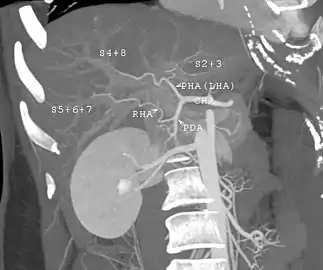

Technique

Before transplantation, liver-support therapy might be indicated (bridging-to-transplantation). Artificial liver support like liver dialysis or bioartificial liver support concepts are currently under preclinical and clinical evaluation. Virtually all liver transplants are done in an orthotopic fashion; that is, the native liver is removed and the new liver is placed in the same anatomic location.[7] The transplant operation can be conceptualized as consisting of the hepatectomy (liver removal) phase, the anhepatic (no liver) phase, and the postimplantation phase. The operation is done through a large incision in the upper abdomen. The hepatectomy involves division of all ligamentous attachments to the liver, as well as the common bile duct, hepatic artery, hepatic vein and portal vein. Usually, the retrohepatic portion of the inferior vena cava is removed along with the liver, although an alternative technique preserves the recipient's vena cava ("piggyback" technique).

The donor's blood in the liver will be replaced by an ice-cold organ storage solution, such as UW (Viaspan) or HTK, until the allograft liver is implanted. Implantation involves anastomoses (connections) of the inferior vena cava, portal vein, and hepatic artery. After blood flow is restored to the new liver, the biliary (bile duct) anastomosis is constructed, either to the recipient's own bile duct or to the small intestine. The surgery usually takes between five and six hours, but may be longer or shorter due to the difficulty of the operation and the experience of the surgeon.

The large majority of liver transplants use the entire liver from a non-living donor for the transplant, particularly for adult recipients. A major advance in pediatric liver transplantation was the development of reduced size liver transplantation, in which a portion of an adult liver is used for an infant or small child. Further developments in this area included split liver transplantation, in which one liver is used for transplants for two recipients, and living donor liver transplantation, in which a portion of a healthy person's liver is removed and used as the allograft. Living donor liver transplantation for pediatric recipients involves removal of approximately 20% of the liver (Couinaud segments 2 and 3).